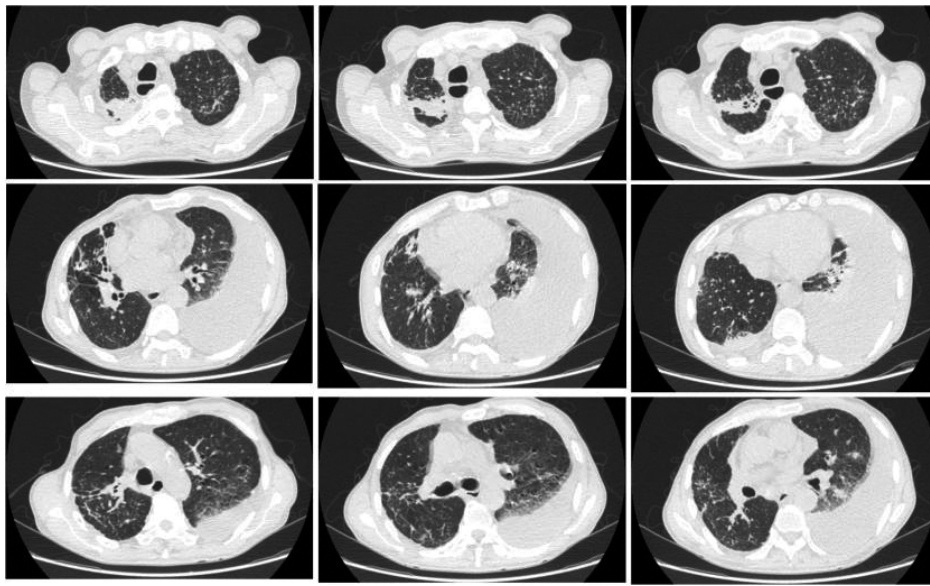

病史摘要:52 岁女性,主因严重突发性呼吸困难、胸部不适、咽喉疼痛就诊。就诊前一周有流涕、咳嗽等症状,前一天因咽喉疼痛加重就诊,甲型流感阳性,对症治疗及用奥司他韦后出院。既往有血脂异常、偏头痛、两年前轻微创伤性颅内出血(保守治疗无后遗症)。 诊疗过程:此次就诊呼吸急促、心动过速、血氧饱和度下降,听诊双侧进气良好伴弥漫性干啰音。动脉血气提示呼吸性碱中毒和缺氧,胸部 X 线和 CT 显示双侧斑